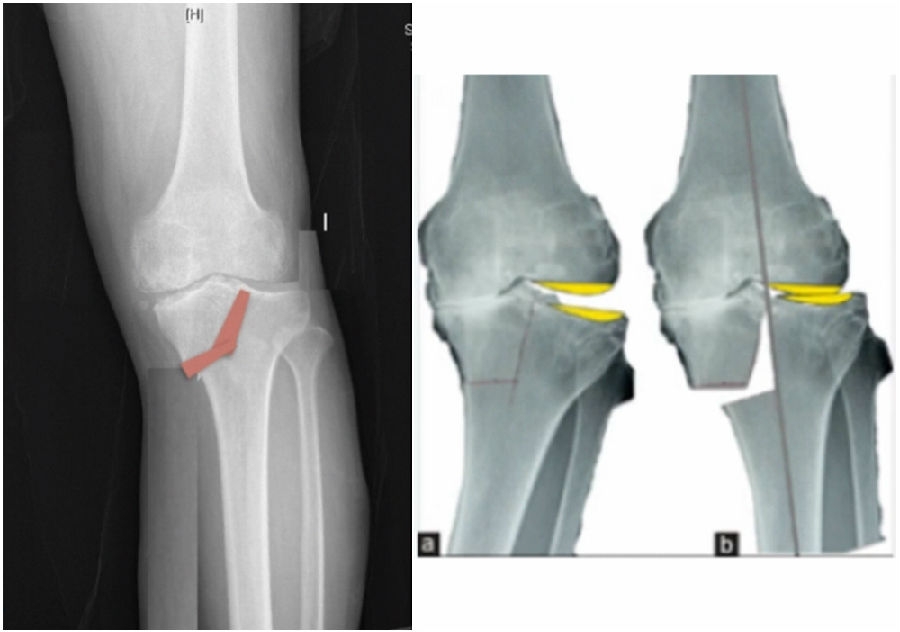

典型病例,女性,56岁,农民右膝内翻18度。

术前影像

术中影像

结合影像学来看,该患者单纯用闭合截骨或开放截骨,对肢体均有影响,所以决定采用混合型截骨。术中混合截骨旋转中心选在内外1/3处,先做闭合楔,然后顺势将开放楔敲开,达到术前设计的目标力线。术后随访力线达到要求。

术后X线